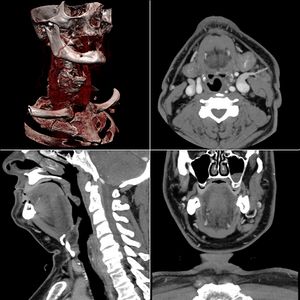

التصوير المَقْطَعي الحاسوبيX-ray computed tomography نظام تصوير بالأشعة السينية، يُسْتخدم لتصوير مختلف أجزاء الجسم مثل الرأس والقلب والبطن. ويستعين الأطباء بالتصوير المقطعي الحاسوبي على تشخيص الأمراض وعلاجها. وتسمى هذه التقنية أيضًا التصوير المقطعي المحوسب أو التصوير المقطعي المحوري المحوسب.

ويستعمل الأطباء فحوص التصوير المقطعي الحاسوبي لتشخيص كثير من الحالات مثل الأورام والإصابات وتجلطات الدم وكسور العظام. ويساعد التصوير المقطعي الحاسوبي أيضًا في معالجة بعض الأمراض، التي قد تتطلب جراحة بطريقة أخرى. فمثلا،ً يمكن للأطباء استعمال التصوير المقطعي الحاسوبي لإرشادهم إلى إدخال القثطار (أنبوب رفيع) إلى خُرّآج في الجسم لسحب الصديد من المنطقة الملوثّة.

تعود تسميتها إلى كون هذه الطريقة تعطى صورًا شعاعية على شكل مقاطع للجسم، يجري التصوير المقطعي المحوسب بواسطة جهاز خاص، يسمى جهاز التصوير المقطعي المحوسب أو الماسحة المقطعية المحوسبة، تتميز هذه الطريقة بدقتها، تعطي صورًا واضحة، ويمكن أن تعطي صورًا لأماكن قد تكون من الصعب تصويرها بالتصوير الشعاعي التقليدي، كذلك يمكن عملها بشكل سريع ودقيق.